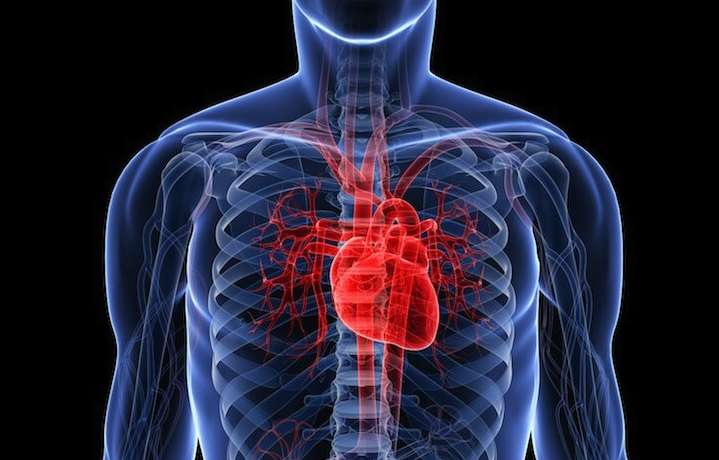

The heart is one of the most important organs in our body, and therefore we should give it proper attention. When heart problems occur, our body gives us clear signals that something is wrong. This article will help you recognize these signals and advise how to properly care for your heart.